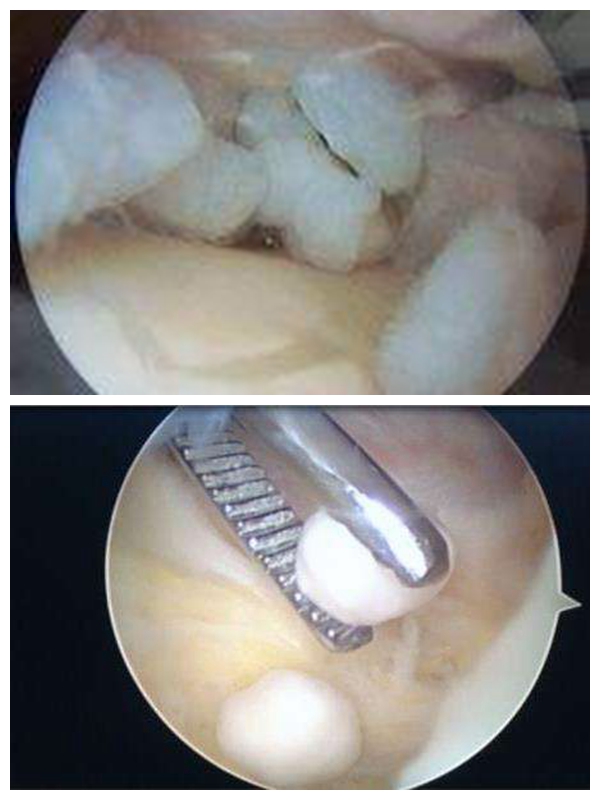

这里说的“小老鼠”不是那种鼠头鼠脑的真“老鼠”,而是一种我们称之为“游离体”的小东西,因为这小东西非常滑,经常在关节里面窜来窜去,非常“狡猾”,所以我们给它取了个非常接地气的名字——“关节鼠”。

关节鼠多发生于膝关节,也见于肘、髋、踝、肩等部位,小的可以只有1mm直径,大的 几厘米,有的单发只有一个,有的多发呈“一窝”。病因主要有膝关节骨性关节炎、关节内感染出血、剥脱性骨软骨炎、骨赘脱落、滑膜性骨软骨瘤病、色结炎等 等,这些疾病常常会导致关节内的组织碎片脱落,像雪花一样散落在关节腔,如果没有及时被吸收,就会像滚雪球一样越滚越大,就形成了游离体——关节鼠。

手术就非常的简单,就是在膝盖打了两个小孔,关节镜下取出来就可以了,术后也不会怎么痛,恢复很快。